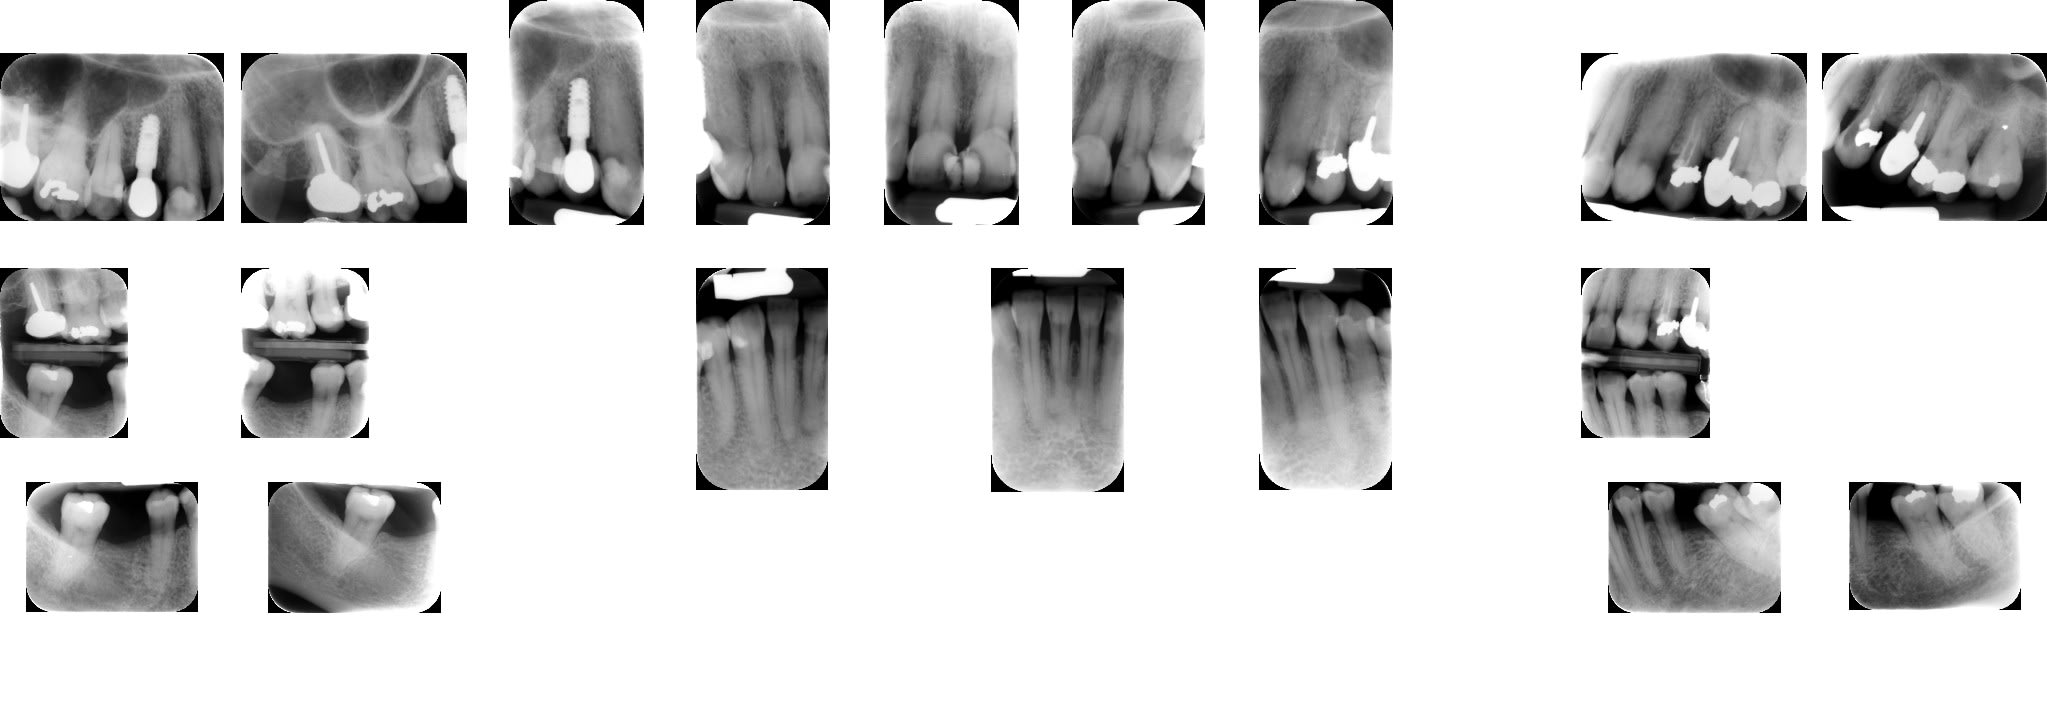

A l'examen clinique, caries de collets typiques, la 45 a du être dévitalisée. Les caries sont plus importantes cliniquement que radiologiquement. Par ex les incisives mand étaient presque intégralement cariées en linguale (?).

Je lui ai fais un bilan et ai décidé de soigner les caries de collet au CVI (GC Equia forte). La 24 et 45 seront couronnées.

Sur un syndrome sec le pouvoir tampon de la salive se casse la figure et la plaque est très adhérente.

Le PH initial des CVI lors du début de la réaction acide base reste assez bas, et sur une dentine jeune et perméable le risque de toxicité pulpaire est élevé; Sur une dentine scléreuse le risque est bien moindre.

le risque du CVI est que son étanchéité n'est acquise que sur une dentine parfaitement saine, or la marge cervicale d'une carie en nappe n'est pas toujours très nette, même avec un fil rétracteur. Le CVI sur des épaisseurs trop fines craquèle.